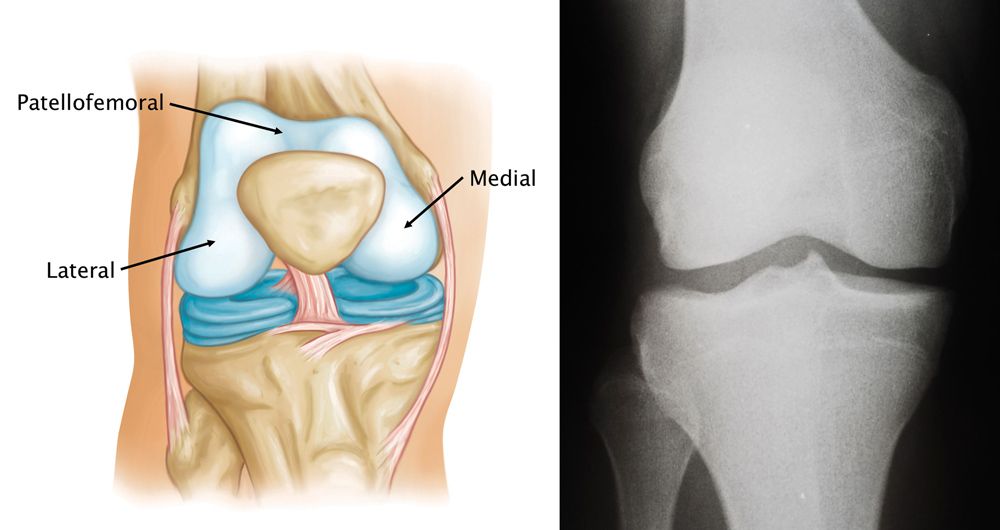

Your knee is divided into three major compartments:

• Medial compartment — the inside part of the knee

• Lateral compartment — the outside part of the knee

• Patellofemoral compartment — the front of the knee between the patella and femur

Normal knee anatomy, including the medial, lateral, and patellofemoral compartments

(Left) A normal knee joint. The medial, lateral and patellofemoral compartments are shown.

(Right) An X-ray of a normal knee showing healthy space between the bones.

X-ray courtesy of Stuart J. Fischer, MD, FAAOS